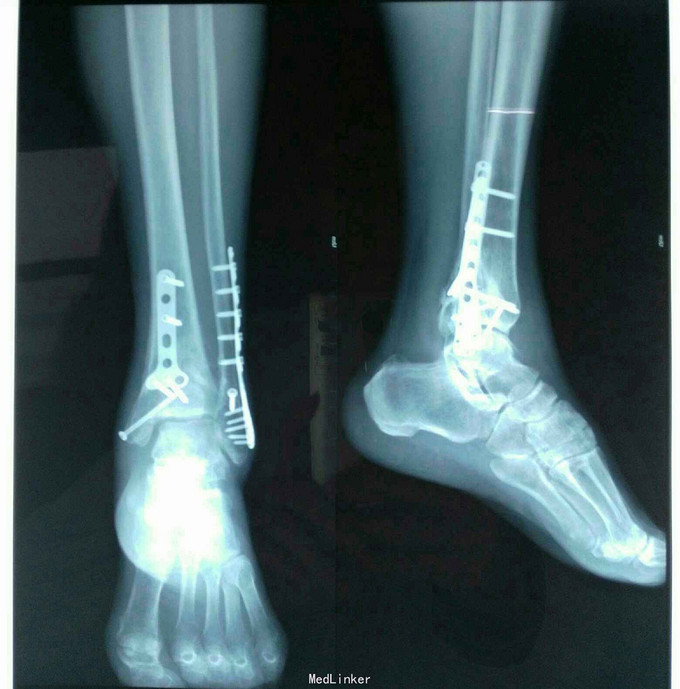

完善相关检查,排除手术禁忌后,行右踝关节粉碎性切开复位没固定 术后片子

术后一个月问诊复查,骨折断端愈合良好